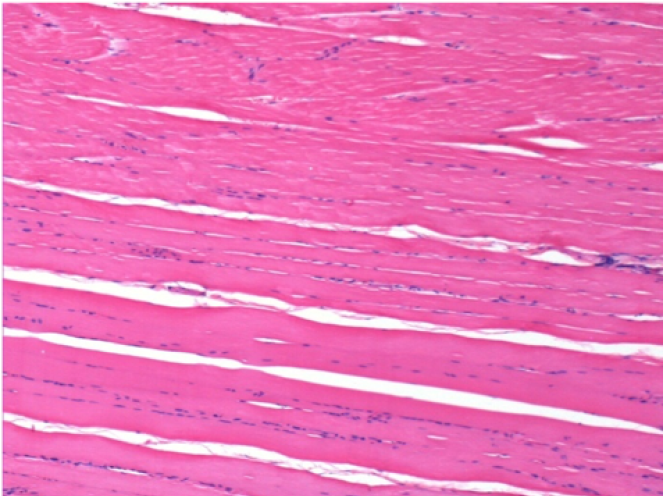

Control

Comment : Nothing to declare after saline solution injection

L:Pretibial-No treatment

R:Pretibial-After 0.1 ml NaCl 0.9% IM